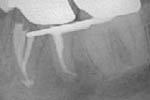

Revisionsbehandlung eines Unterkiefermolaren (37) vor geplanter Überkronung (Dr. Maik Göbbels) Download